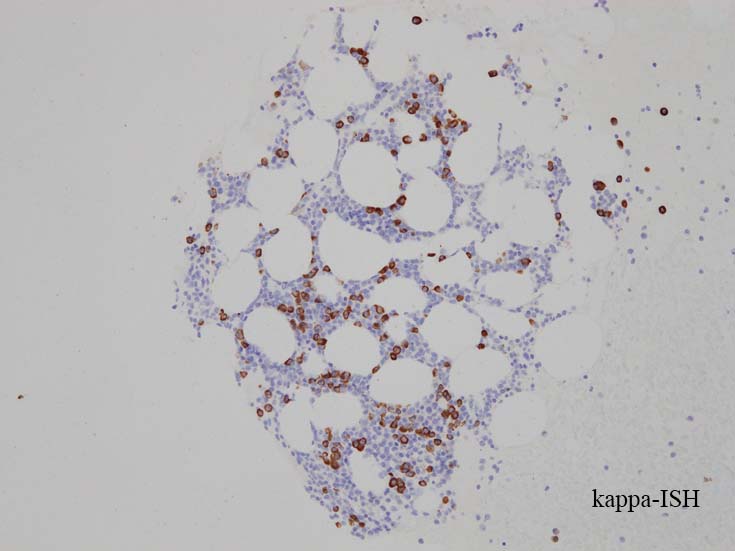

CD138陽性細胞が増加している. CD19陽性細胞が多く認められ, 明かなkappa, lambda restrictionは見られない. polyclonal proliferationと考えられる.

形質細胞の凝集増加がめだつ.